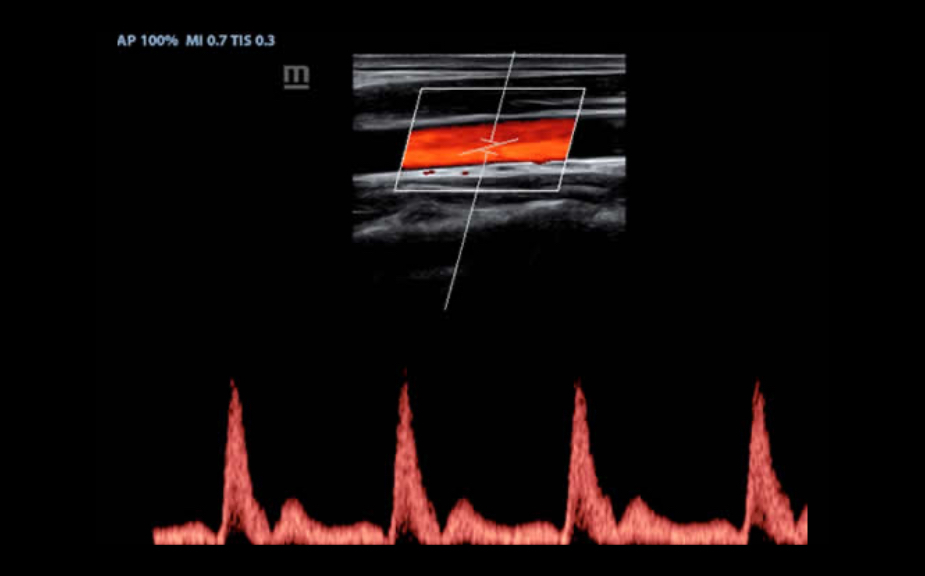

IMT (Intima-Media Kal?nl?k)

GÞvenilir karotid durum bilgisi sa?layan anterior ve posterior duvar kal?nl???n?n otomatik ?l?ÞmÞ.